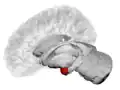

Location of the amygdalae in the human brain

The amygdala (/əˈmɪɡdələ/; pl.: amygdalae /əˈmɪɡdəli, -l/ or amygdalas; also corpus amygdaloideum; Latin from Greek, ἀμυγδαλή, amygdalē, 'almond', 'tonsil'[1]) is a paired nuclear complex present in the cerebral hemispheres of vertebrates. It is considered part of the limbic system.[2] In primates, it is located medially within the temporal lobes.[3] It consists of many nuclei, each made up of further subnuclei. The subdivision most commonly made is into the basolateral, central, cortical, and medial nuclei together with the intercalated cell clusters.[4] The amygdala has a primary role in the processing of memory, decision-making, and emotional responses (including fear, anxiety, and aggression). The amygdala was first identified and named by Karl Friedrich Burdach in 1822.[5]